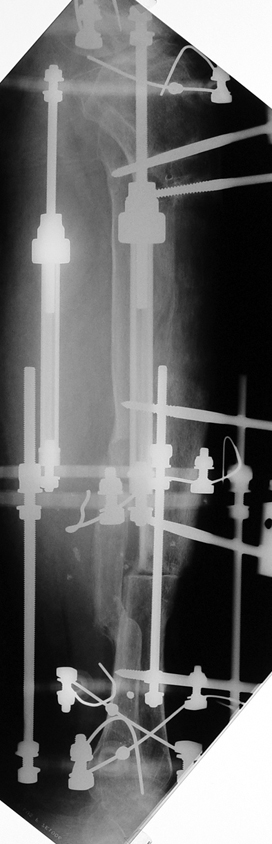

Appropriate radical debridement necessitates excision of all necrotic bone and soft tissues, and frequently causes instability at the involved extremity. The remaining bone and soft tissue defect has to be fixed and reconstructed. The distraction osteogenesis method of Ilizarov is used successfully for achievement of union, correction of the deformity, elimination of limb length inequality and reconstruction of segmental bone defects.

The duration of external fixation (external fixation index) depends on the amount of distraction required, and the extremity is prone to complications during this period. After the distraction phase is completed, the external fixator remains in place during the consolidation phase, which lasts twice as long as the distraction phase; but this period is hardly tolerated. If the external fixator is removed before sufficient consolidation is achieved, fractures, deformity and shortness will be the result. In our department, ‘lenghthening over nail’ method is used in order to decrease the external fixation index and increase patient comfort and activity level. In this method, the intramedullary nail is statically locked after the completion of the distraction phase, and external fixator is removed. The extremity is stabilized by the intramedullary nail during consolidation phase. In this way, complications due to long external fixation index or early removal of the external fixator are avoided.